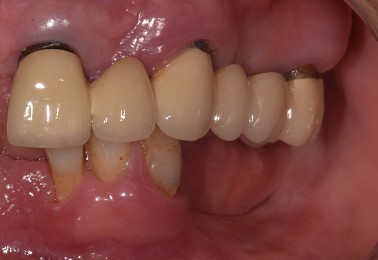

Una paziente di 65 anni si presentava presso la nostra clinica con ampie aree edentule (1° e 3° quadrante), un ponte con mobilità nel 2° quadrante e denti inferiori con scarso supporto parodontale ad eccezione del dente 46 (Fig. 1 a,b,c,d). Dopo un'accurata anamnesi ed esame della CBCT (CS9600®, Carestream Dental, Atlanta, USA) (Fig. 1d), si optava per estrarre le radici e i denti con una prognosi sfavorevole, lasciando 4 molari che credevamo potessero essere conservati (denti 16,17, 26 e 47) al fine di mantenere la dimensione verticale di occlusione (DVO) originale. Si progettava il posizionamento di 12 impianti: 6 impianti nella mascella e 6 nell'arcata inferiore.

Situazione pre operatoria 1

Fig. 1(a)

Situazione pre operatoria 2

Fig. 1(b)